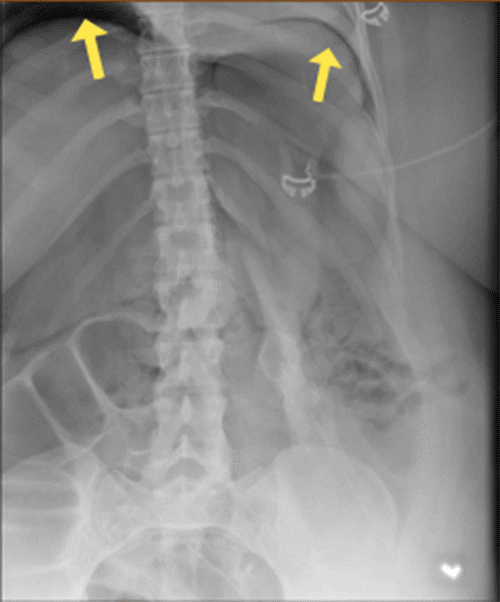

Within 30 minutes of arrival to the SICU, the patient’s abdomen was noted to be distended and firm. Her peak inspiratory pressures (PIP) were elevated, ranging between 55 to 60, and she was hypoxic with oxygen saturation in the 70s and 80s. Arterial blood gas (ABG) revealed a pH of 7.32, PaCO2 of 70, and bicarbonate level of 35. The PAO2/FiO2 ratio was 87. A chest X-ray (CXR) (Figure 1) showed the tracheostomy tube placed in the right mainstem bronchus. An urgent bedside tracheostomy exchange was performed by the ENT, replacing the tube with a shorter one. A subsequent CXR also revealed pneumoperitoneum, with free air observed under both hemidiaphragm, a finding that was confirmed by abdominal X-ray (AXR) (Figure 2).

Figure 2. Postoperative Abdominal X-ray. Published with Permission

Imaging confirms the presence of free intraperitoneal air